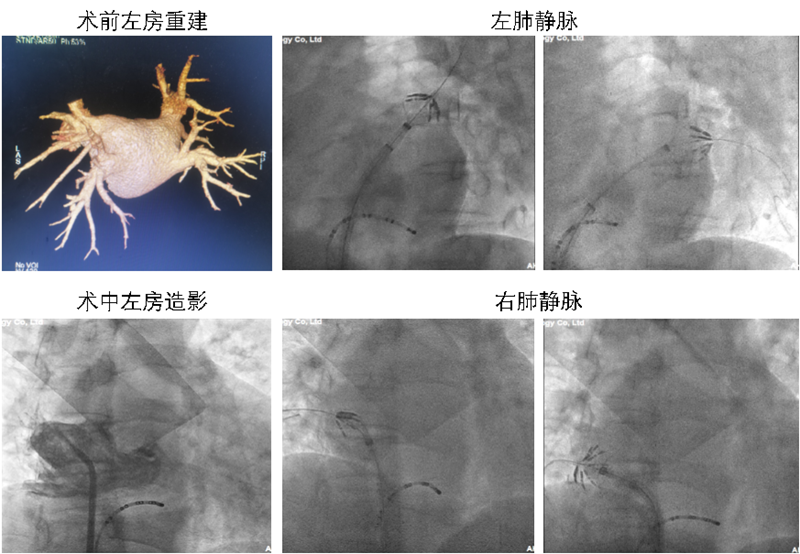

来自安徽泗县的42岁男性患者李某某,因反复心慌伴胸闷气喘半年余,就诊于心血管内科门诊,张恒主任经初步检查后诊断为:阵发性心房颤动,高血压病3级。患者入院后,进行了心脏彩超检查、肺静脉+左心房三维重建等全面检查,为了带给患者更安全、更高效的治疗结果,张恒主任及电生理团队充分评估检查结果并结合患者自身状况,经反复讨论后决定,为患者实施局麻下房颤PFA治疗。

手术中,该患者消融放电总时长仅为4.92秒,术中可见放电后肺静脉电位即刻消失,患者无明显痛感,不仅消融时间大大缩短,也无毗邻组织的损伤,提高了安全性,术后患者恢复良好,隔日,患者即出院恢复日常生活。